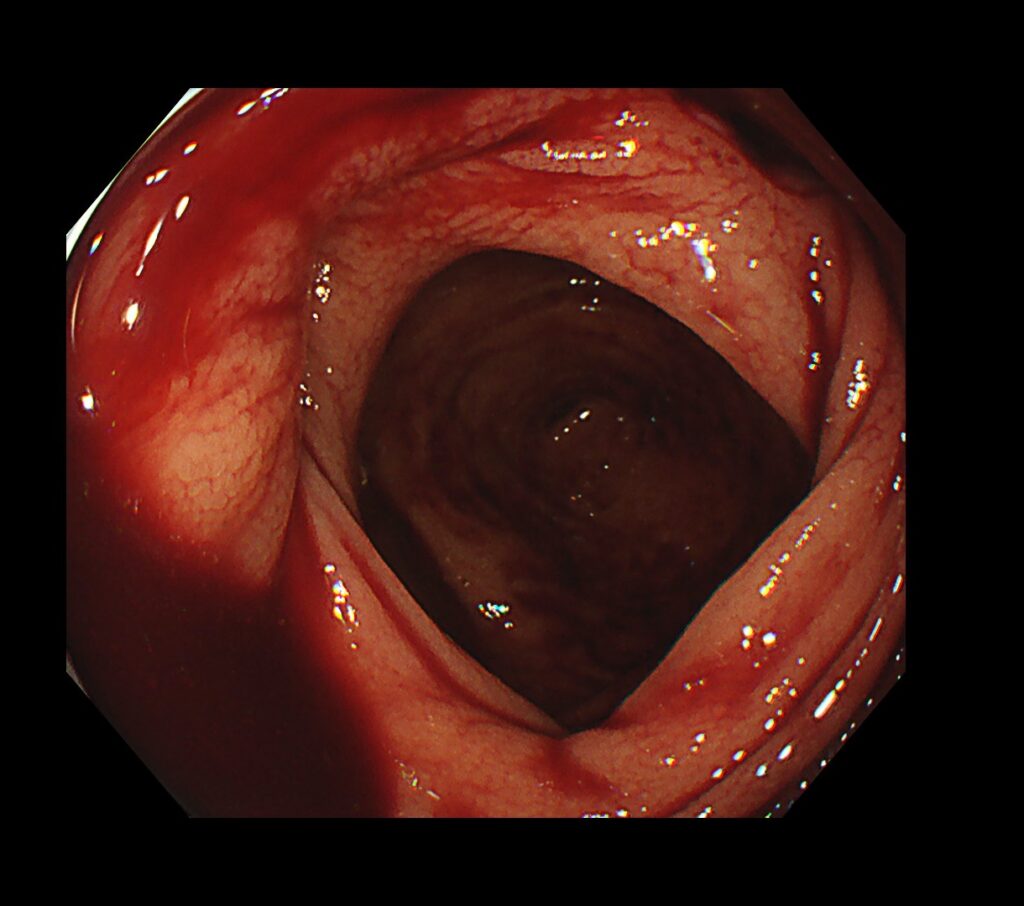

大量の便とコアグラ(血糊)の中、盲腸まで挿入すると新鮮血のたまり場がありました。

つまり、責任憩室が近くにある+現在進行系で動脈出血している可能性を示唆する所見です。